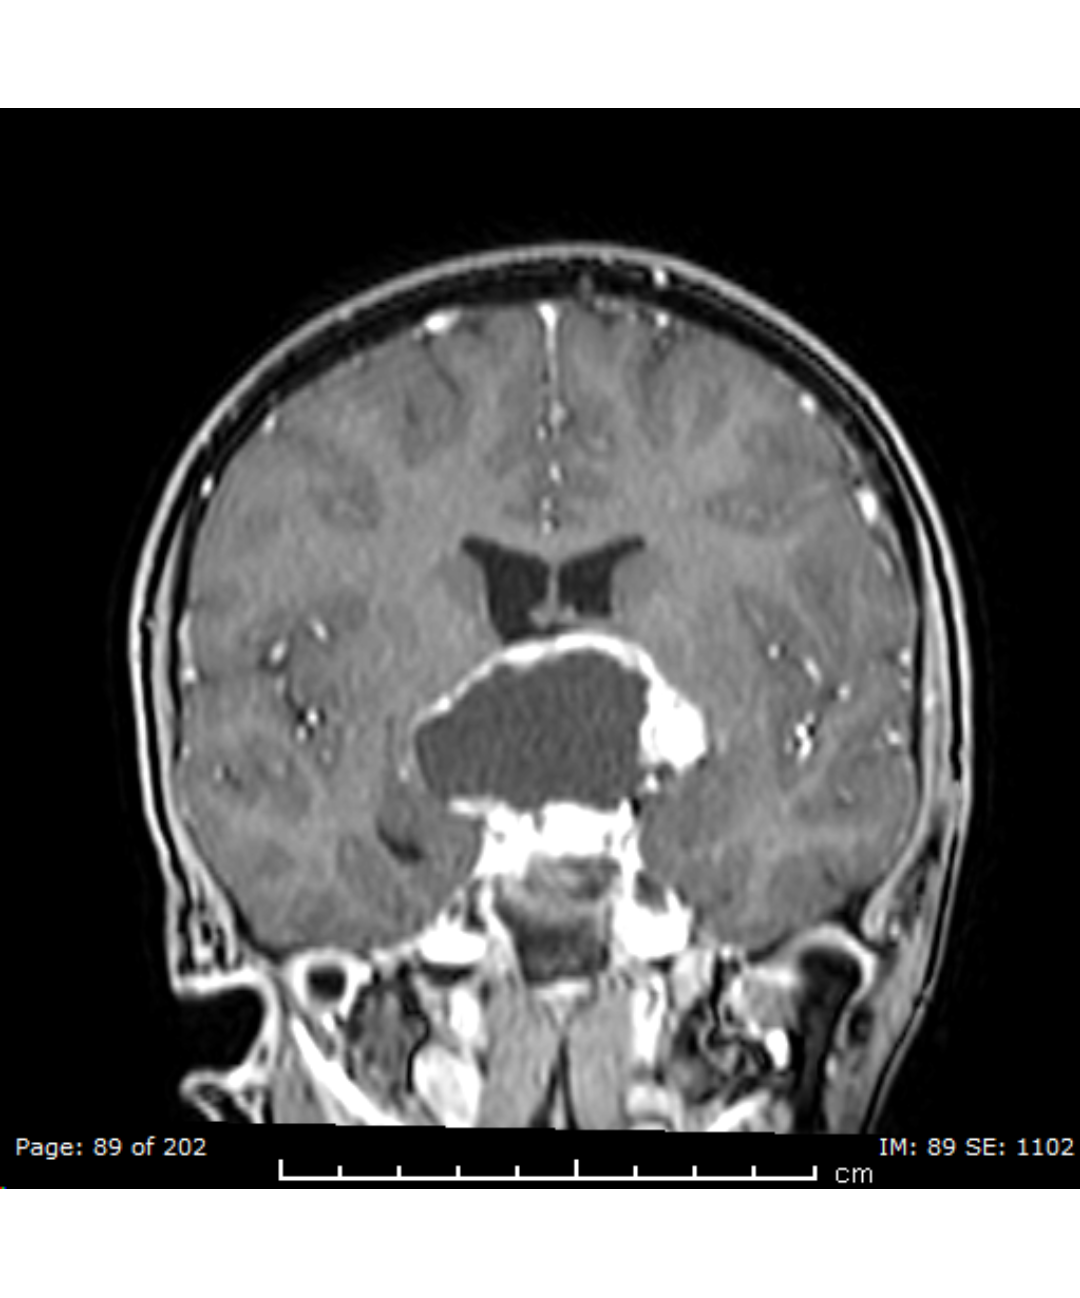

An international multidisciplinary meeting for clinical specialists and scientists to address pediatric craniopharyngioma, establish a multidisciplinary community focused on ACP and to share current state regarding the diagnosis and care of children with Craniopharyngioma, and to design and plan upcoming research efforts, both clinical and basic.